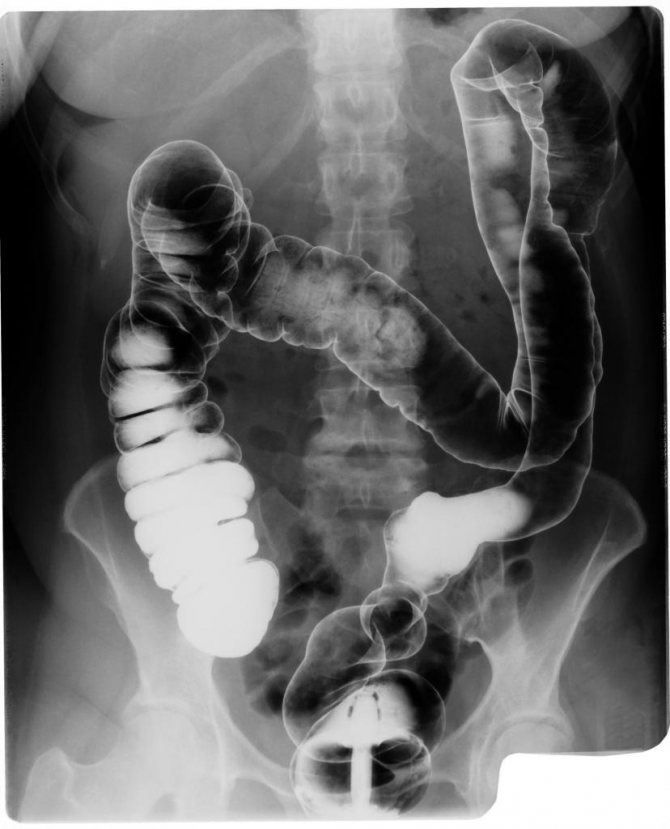

Ирригоскопия как альтернатива колоноскопии. Преимущества и недостатки

Это еще один метод обследования толстого кишечника с помощью рентгеновского излучения. Один из недостатков его как раз в этом и состоит, облучение не безвредно для человека, но надо отметить, доза не больше, чем при любом другом рентгене костей и других органов.

Во время ирригоскопии по специальной трубке толстый кишечник заполняют контрастным веществом (1,5-2 литра). В этот момент врач делает несколько рентгеновских снимков. После опорожнения кишечника его наполняют воздухом для распрямления стенок, и врач вновь делает снимки.

Отличие ирригоскопии от колоноскопии в том, что первая проводится без наркоза. Если человек тяжело переносит анестезию, то стоит задуматься о проведении первой. По подготовке процедуры схожие, обе предполагают диету и прием слабительных накануне.

Диагностика воспаления червеобразного отростка (аппендицита) достаточно затруднительна из-за расплывчатых симптомов. Специалисты утверждают, что колоноскопия и ирригоскопия покажут аппендицит. А вот анализы крови и мочи, как правило, патологических процессов в толстом кишечнике не покажут.